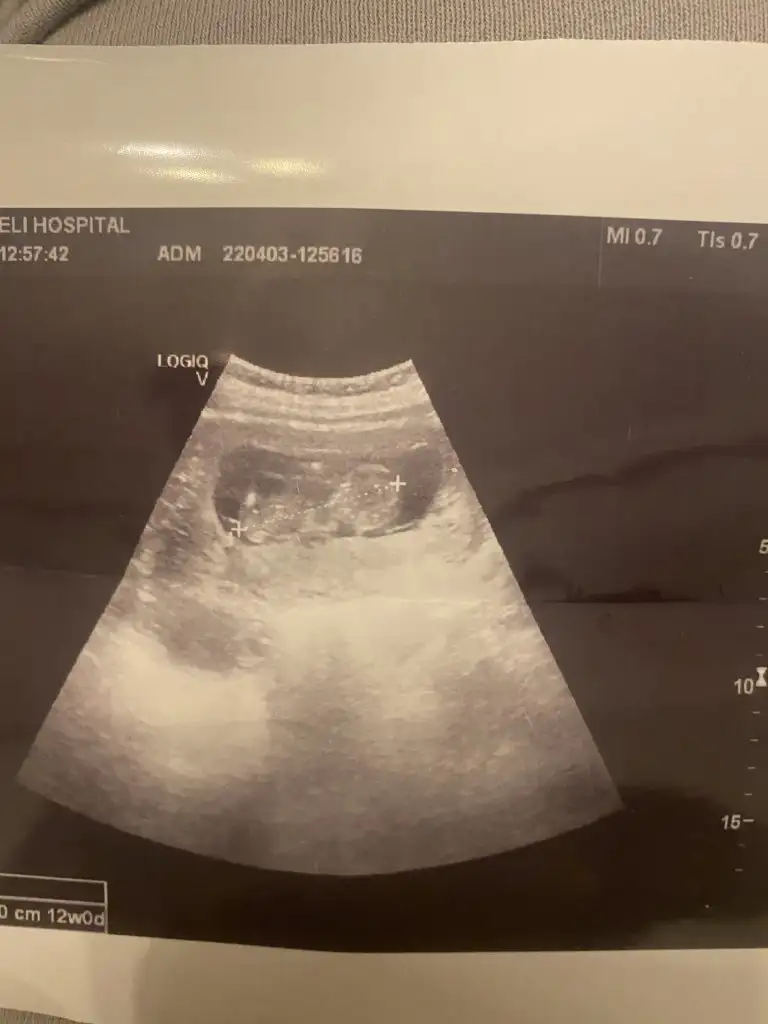

Pasha22 Pasha22 canım bir yakınım ultrason kağıdını atsam bakar mısın cinsiyete 7+4 günlük karından bakılmış 🤩